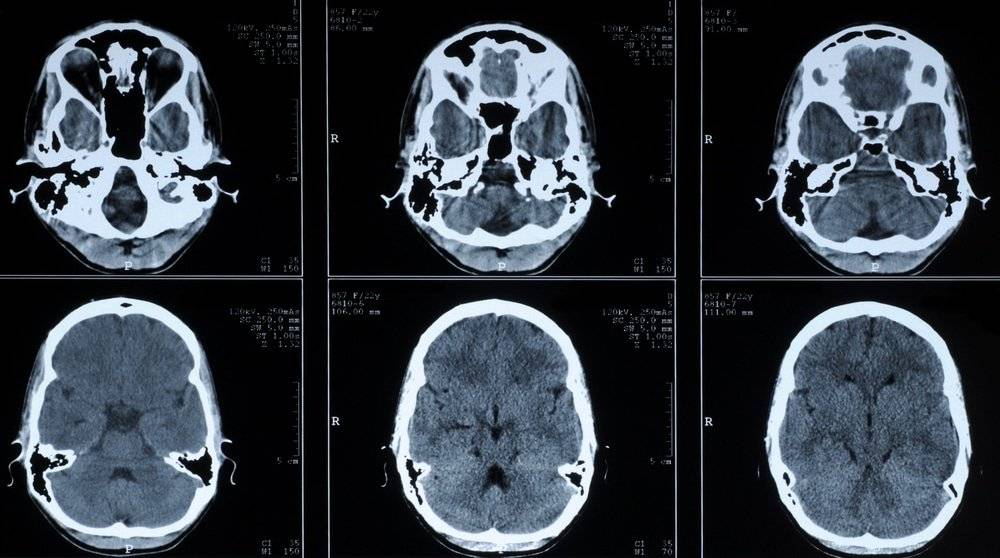

Энцефалопатия – поражение головного мозга не воспалительного характера, в основе которого лежит гипоксия или кислородное голодание мозга. Болезнь может быть врожденной или приобретенной. В первом случае развивается на фоне патологии беременности матери, родовой травмы или генетической предрасположенности. Во втором случае факторами развития выступают травмы головы, вирусные инфекции, сердечно-сосудистые заболевания, алкоголизм и наркомания. В соответствии с причинами, вызвавшими развитие патологии, выделяют несколько видов энцефалопатии, в том числе резидуальную и дисциркуляторную.